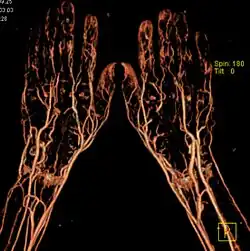

КТ-ангиография позволяет получить послойную серию изображений кровеносных сосудов; на основе полученных данных посредством компьютерной постобработки с 3D-реконструкцией строится трёхмерная модель кровеносной системы.

Спиральная КТ-ангиография — одно из последних достижений рентгеновской компьютерной томографии. Исследование проводится в амбулаторных условиях. В локтевую вену вводится йодсодержащий контрастный препарат в объёме около 100 мл. В момент введения контрастного вещества делают серию сканирований исследуемого участка.